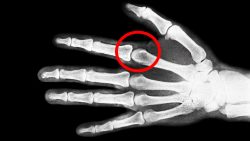

Ist Fingerknacken Gefährlich

Viele können es machen und vielen geht das Geräusch dabei auf den Keks, wenn jemand mit den Fingern knackt. Es spalten sich ja die Lager…